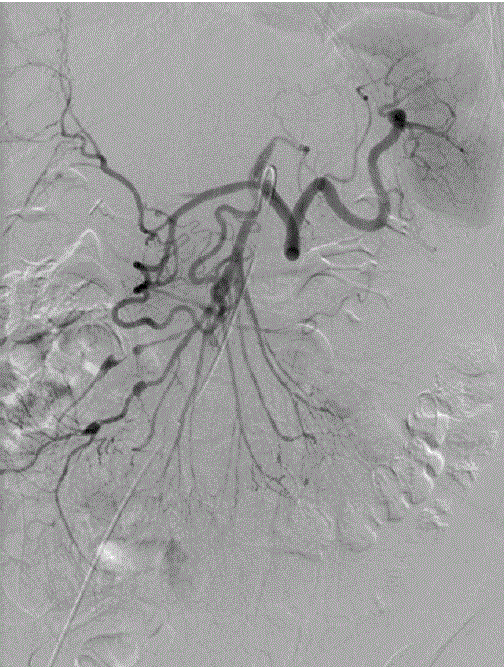

demonstrating

Figure 3. Superior mesenteric angiogram demonstrating vascular irregularity and pseudoaneurysm formation in the right colic, ileocolic and ileojejunal branches, as well as irregularity and pseudoaneurysm formation of multiple right hepatic arteries.